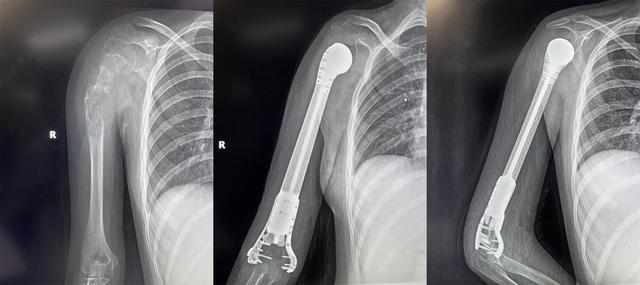

13歲少女患骨肉瘤面臨截肢,3D打印肱骨假體治療成功保肢

2022年4月19日,獲悉,西安市紅會醫(yī)院骨病腫瘤科為一名13歲小患者成功實施了肱骨惡性腫瘤切除3D打印假體重建術(shù)。165751qartxm1zze19w2ha.jpg

小欣(化名)因右肱骨中上段腫瘤,飽受疾病折磨,幾經(jīng)輾轉(zhuǎn)后來到西安市紅會醫(yī)院就醫(yī),活檢確診為 右肱骨中上段骨肉瘤 。

骨病腫瘤科楊團民主任介紹,骨肉瘤是一種好發(fā)于兒童長骨的骨端高度惡性的原發(fā)性腫瘤,治療原則為手術(shù)結(jié)合化療、放療綜合治療。 由于腫瘤范圍較大沒有生物重建可能,也沒有相關(guān)腫瘤假體,保肢難度很大,一直是業(yè)內(nèi)難題,所以普遍選擇截肢。 165751f8i13tpusqaqduut.jpg

對于一個13歲的女孩來說,截肢必然會對孩子的心靈帶來巨大陰影,同時小欣父母表達了強烈的保肢意愿后,最終決定選擇保肢方案。針對小欣的具體病情,骨病腫瘤科楊團民主任帶領(lǐng)團隊成員王志酬、黃桂林、邵宇雄、李爭爭主治醫(yī)師等人,經(jīng)過認真病例討論,決定 新輔助化療后,手術(shù)切除右肱骨骨腫瘤 。發(fā)揮3D打印在骨科領(lǐng)域優(yōu)勢,設(shè)計個體化3D打印肱骨上段鈦合金假體,結(jié)合人工肩關(guān)節(jié)技術(shù),保留部分正常骨、患肢長度,可實現(xiàn)肱骨重建。165751kg0sm7xwzxmksk7w.jpg

術(shù)前,經(jīng)精密計算機輔助設(shè)計、影像學(xué)數(shù)據(jù)鏡像反求和鈦合金3D打印,假體的3D打印仿骨小梁端和截骨端可以完美貼合,使骨長入得以實現(xiàn),達到生物重建效果。這樣既保留了關(guān)節(jié),也減少假體松動的發(fā)生率。同時空隙結(jié)構(gòu)利于軟組織長入。手術(shù)當日,在麻醉科配合下,楊團民主任團隊密切協(xié)作、精細操作,依次完成腫瘤切除、3D打印假體植入、軟組織重建系列操作。歷時3小時,順利完成醫(yī)院首例3D打印肱骨假體治療肱骨骨肉瘤手術(shù)。

目前,小欣全身狀況良好,正在進行積極的功能鍛煉,力爭盡早實現(xiàn)正常生活。